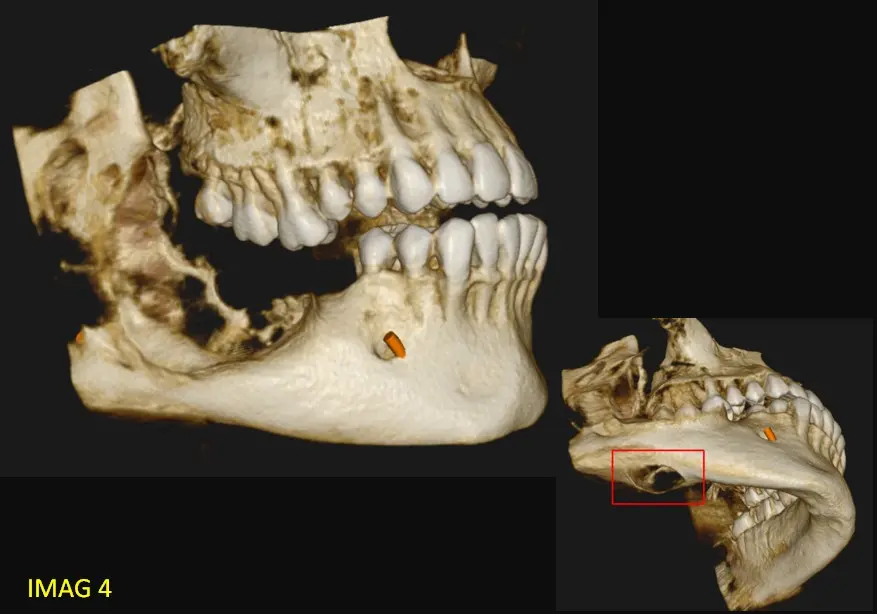

En los cortes sagitales y axiales de CBCT (ver imagen 2 y 3) se evidencia un marcado desplazamiento del conducto dentario inferior hacia el borde basal, acompañado de adelgazamiento y perforación de la cortical ósea, visible en la reconstrucción multiplanar (ver imagen 4). El contenido de la lesión es homogéneo, no se identifican tabiques internos ni calcificaciones que sugieran una lesión fibro-ósea, y la expansión y perforación cortical indican un comportamiento localmente agresivo. Por la combinación de las características: lesión unilocular, sin relación dentaria, desplazamiento del conducto y perforación cortical— el diagnóstico más probable es un ameloblastoma unicístico, considerando como segundo diagnóstico diferencial un queratoquiste odontogénico.